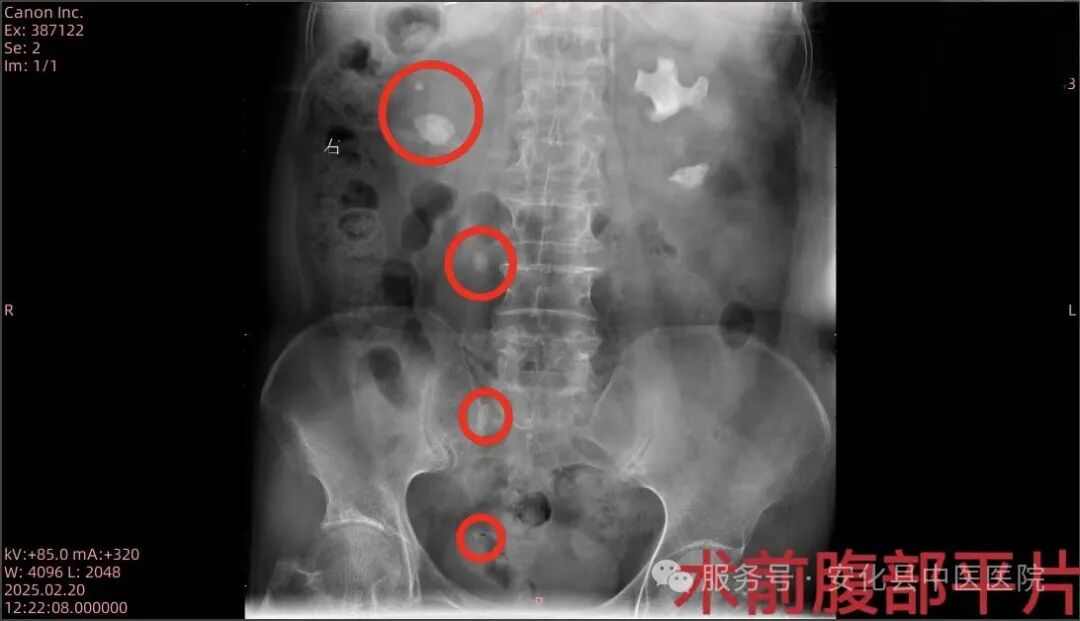

患者,女,70岁,因“右侧腰腹部疼痛不适2天”入住我院泌尿外科,泌尿系CT检查提示“右肾多发性结石并右肾中度积水、右侧输尿管多发性结石、左肾多发性结石”。为减少创伤,保护患者肾脏功能,泌尿外科主任朱武、主治医师邓智勇多次研究讨论该病例治疗方案,最终决定行右侧经尿道可弯曲负压吸引鞘+输尿管软镜下钬激光取石术,术后患者恢复良好。输尿管鞘是什么【技术突破】无创取石新利器——安化县中医医院成功开展可弯曲负压吸引鞘联合输尿管软镜钬激光碎石取石术•“卓越服务”系列报道(十六)_https://www.jmylbn.com_新闻资讯_第3张输尿管鞘是什么【技术突破】无创取石新利器——安化县中医医院成功开展可弯曲负压吸引鞘联合输尿管软镜钬激光碎石取石术•“卓越服务”系列报道(十六)_https://www.jmylbn.com_新闻资讯_第4张

▲术前术后腹部平片对比